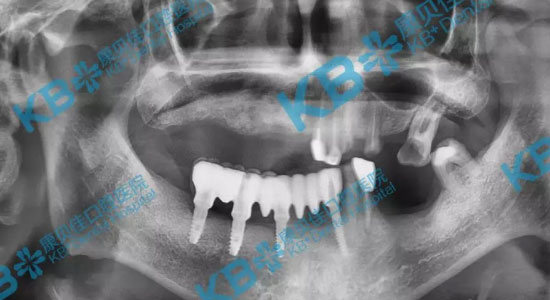

口腔CT拍片后,任势雄博士表示杨叔叔缺牙数量多,缺失的时间也比较久,牙槽骨已经严重萎缩,骨量不足,适合方案是半/全口微创即刻种植。任势雄博士亲自设计了种植方案,将部分坏牙拔除后,上下各植入4颗种植体,为杨叔叔达到了恢复全口牙齿的效果,恢复咀嚼功能。